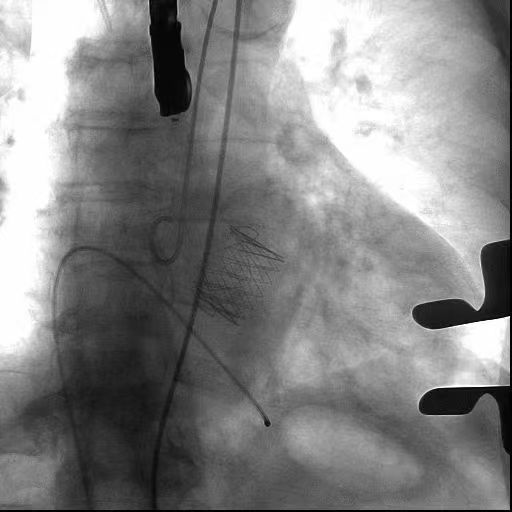

术中瓣膜释放演示:

患者男性84岁,3年来因胸闷,憋喘等症状于外院多次就诊,诊断为心力衰竭,药物治疗后病情反复,患者苦不堪言。此次入院后心脏超声提示主动脉瓣重度关闭不全,二尖瓣中—重度关闭不全,射血分数35%。科内讨论鉴于患者高龄,伴发疾病多,难以耐受常规开胸体外循环辅助的瓣膜置换手术,经心尖TAVR手术是其最佳选择。在医院领导支持下,医疗部组织全院讨论,多次召开协调会,经精心准备8月24日手术在杂交手术室如期进行,全麻后手术顺利实施,食道超声及主动脉根部造影显示瓣膜位置良好、开闭自如,复查超声提示主动脉瓣无反流,二尖瓣反流减轻,心功能改善,9月5日顺利康复出院。